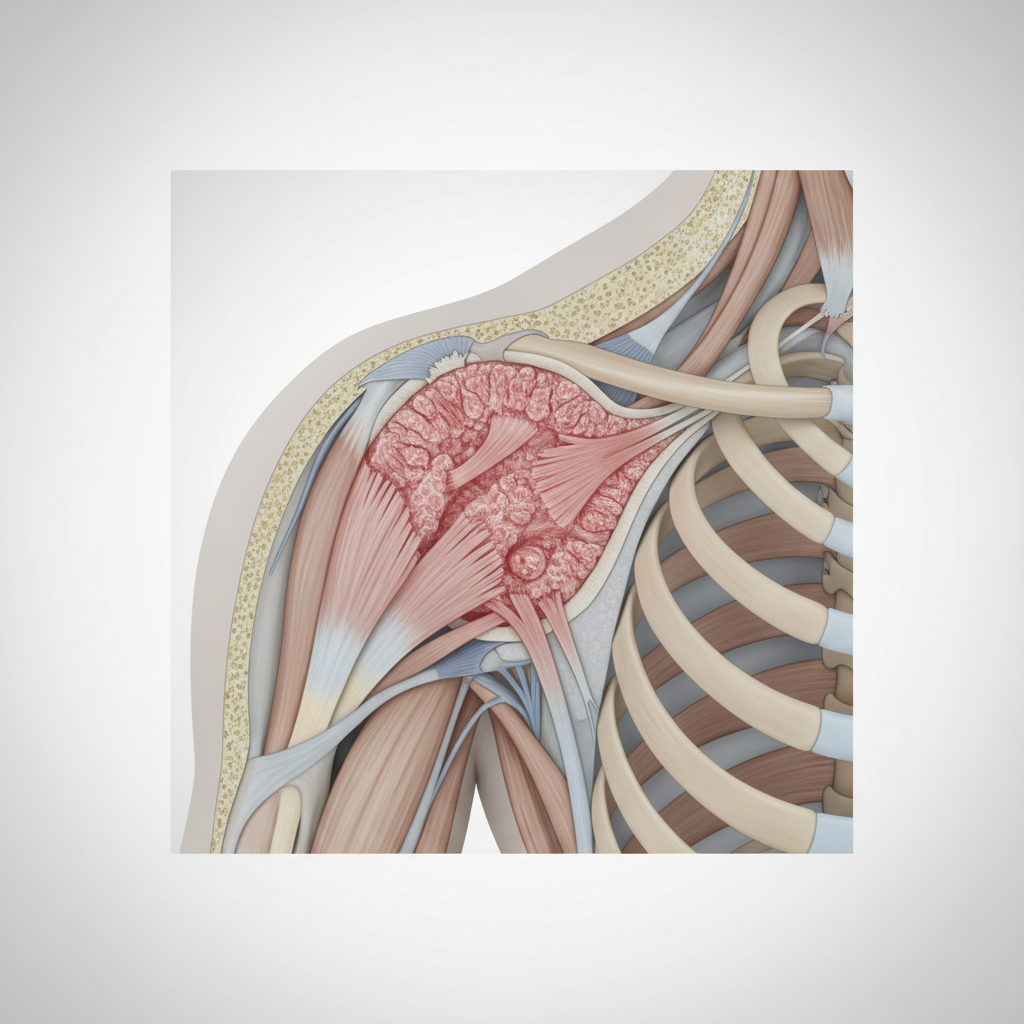

ICF: Body Functions & Structures

• Impairments:<br>• Shoulder and upper arm pain<br>• Progressive stiffness<br>• Reduced AROM and PROM<br>• Capsular tightness<br>• Secondary muscle weakness<br>• Night pain and sleep disturbance

Expected Findings

• Marked reduction of AROM and PROM<br>• Capsular pattern limitation:<br> External Rotation > Abduction > Internal Rotation<br>• Pain at end range of motion<br>• Muscle weakness due to pain inhibition